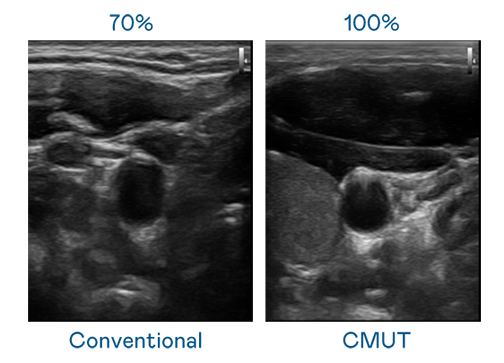

CMUT 技术是一种用电容式微机电元件来产生超音波讯号的技术。与传统 PZT 压电式技术相比,CMUT 频宽增加 30%,更宽频的超音波讯号让影像解析度大幅提升,是实现高影像品质医疗超音波扫描、促进精准医疗发展的关键技术。

大频宽带来超清晰影像

超音波影像的解析度高低,首先取决于探头能发出的讯号频宽。玩彩网· CMUT 可提供高清晰的超音波讯号,提供高频宽、高灵敏度、影像纹理细节更高的超音波影像,协助医护人员缩短影像判读时间及利用精准的医疗影像进行诊断。